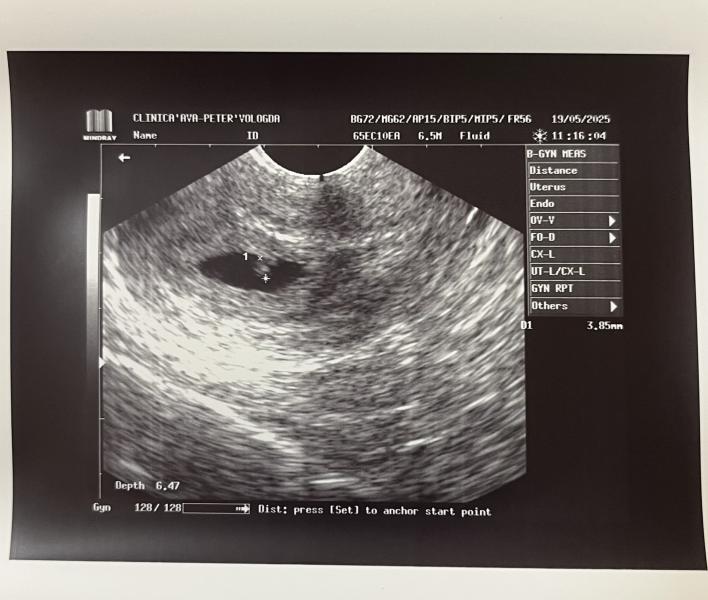

Все прошло отлично! Эмбриона пока не видно, но сказали, что вот вот появится)

По узи срок 5.2

По месячным 6